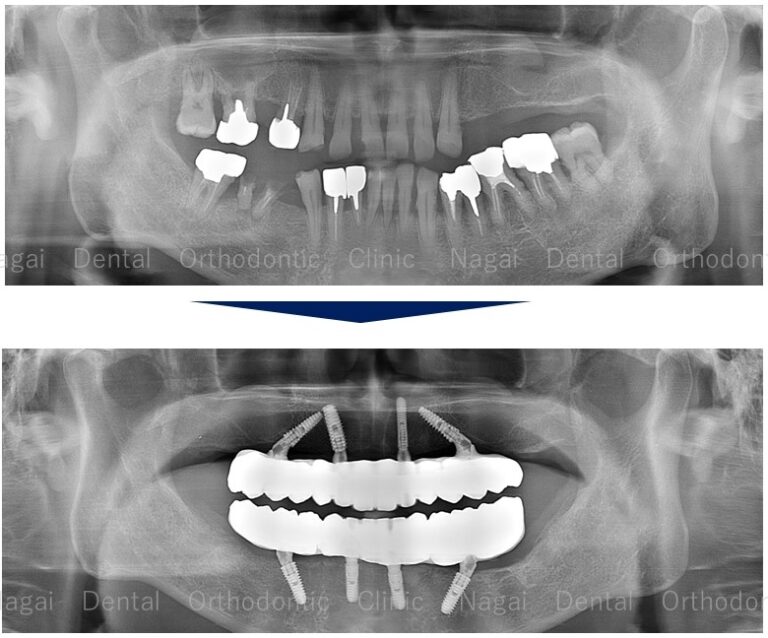

【口腔内の詳細変化】

▲重度歯周病に伴う歯の動揺と咀嚼機能低下の改善を図りました

▲インプラントによる固定式補綴物で、全体的な咬合の再構築を目指しました

| 治療内容 | 上下顎:オールオンフォー(上顎:インプラント5本、下顎:インプラント4本) |

|---|---|

| 年齢/性別 | 60代/男性 |

| 背景 | 臼歯部の多数歯欠損および残存歯の重度歯周病による著しい動揺があり、咀嚼できる食品が制限されている(柔らかいものしか噛めない)ことを主訴に来院されました。長期間歯科受診から遠ざかっておられましたが、咀嚼機能の改善を希望されての受診でした。 |

| 治療期間 | 約9か月(出張に伴う期間調整3ヶ月を含む/通院13回) |

| 費用 | 5,500,000円(税込)(片顎 2,750,000円×2) |

| リスク/副作用 | インプラント手術は、ご高齢の方や全身状態(持病など)によっては適応とならない場合があります。また、術後の口腔清掃を怠ると天然歯の歯周病に似たインプラント周囲炎が起こる可能性があるため、日々のセルフケアと定期的なメンテナンスが必要です。 |